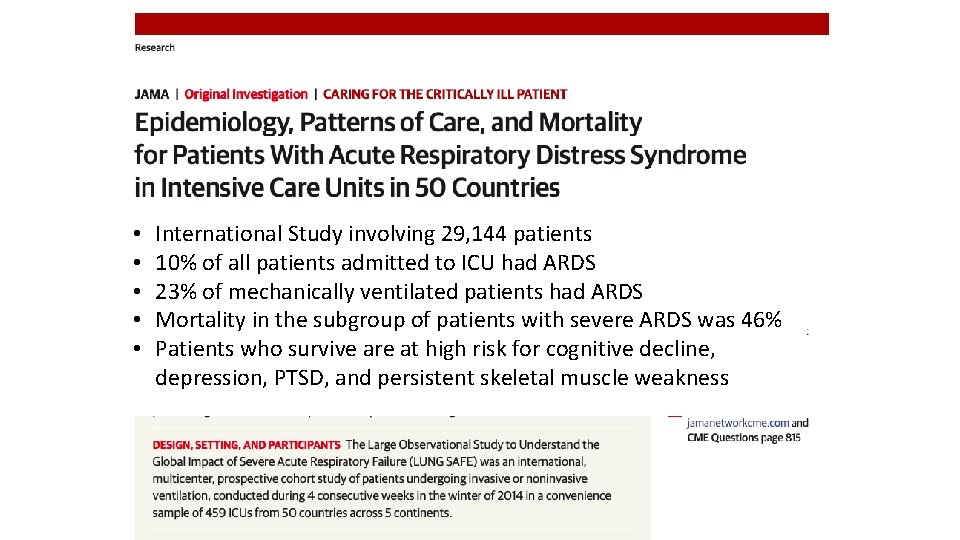

• • • International Study involving 29, 144 patients 10% of all patients admitted to ICU had ARDS 23% of mechanically ventilated patients had ARDS Mortality in the subgroup of patients with severe ARDS was 46% Patients who survive are at high risk for cognitive decline, depression, PTSD, and persistent skeletal muscle weakness

Acute Respiratory Distress Syndrome • Highest rates reported in Australia and the USA • Underuse of currently recommended lung-protective practices was seen across the severity spectrum